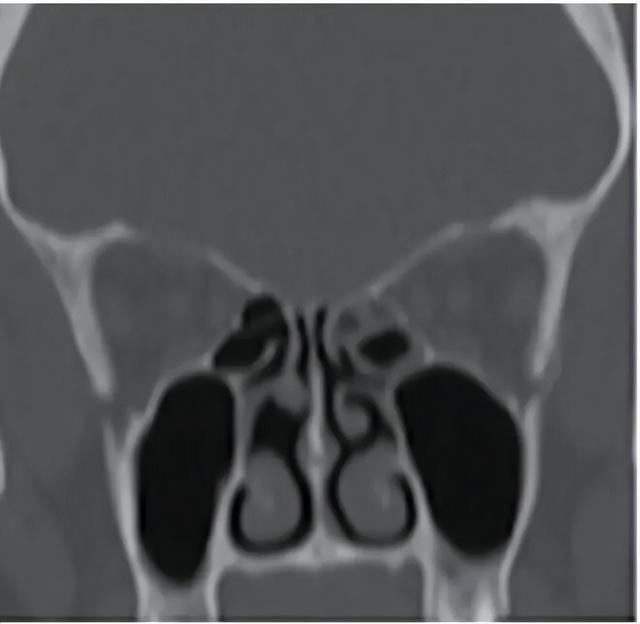

一位挖鼻癖患者的鼻窦鼻腔 CT,显示中鼻甲头部缺失。图源:参考文献[6]

如果一个人出现以下情况,就不再只是普通习惯:挖鼻行为难以控制、频繁导致出血或结痂、鼻腔结构出现损伤、或者伴随明显焦虑和心理压力。

这时更合理的做法,是寻求耳鼻喉科或心理科的评估,而不是单纯依靠自我克制。